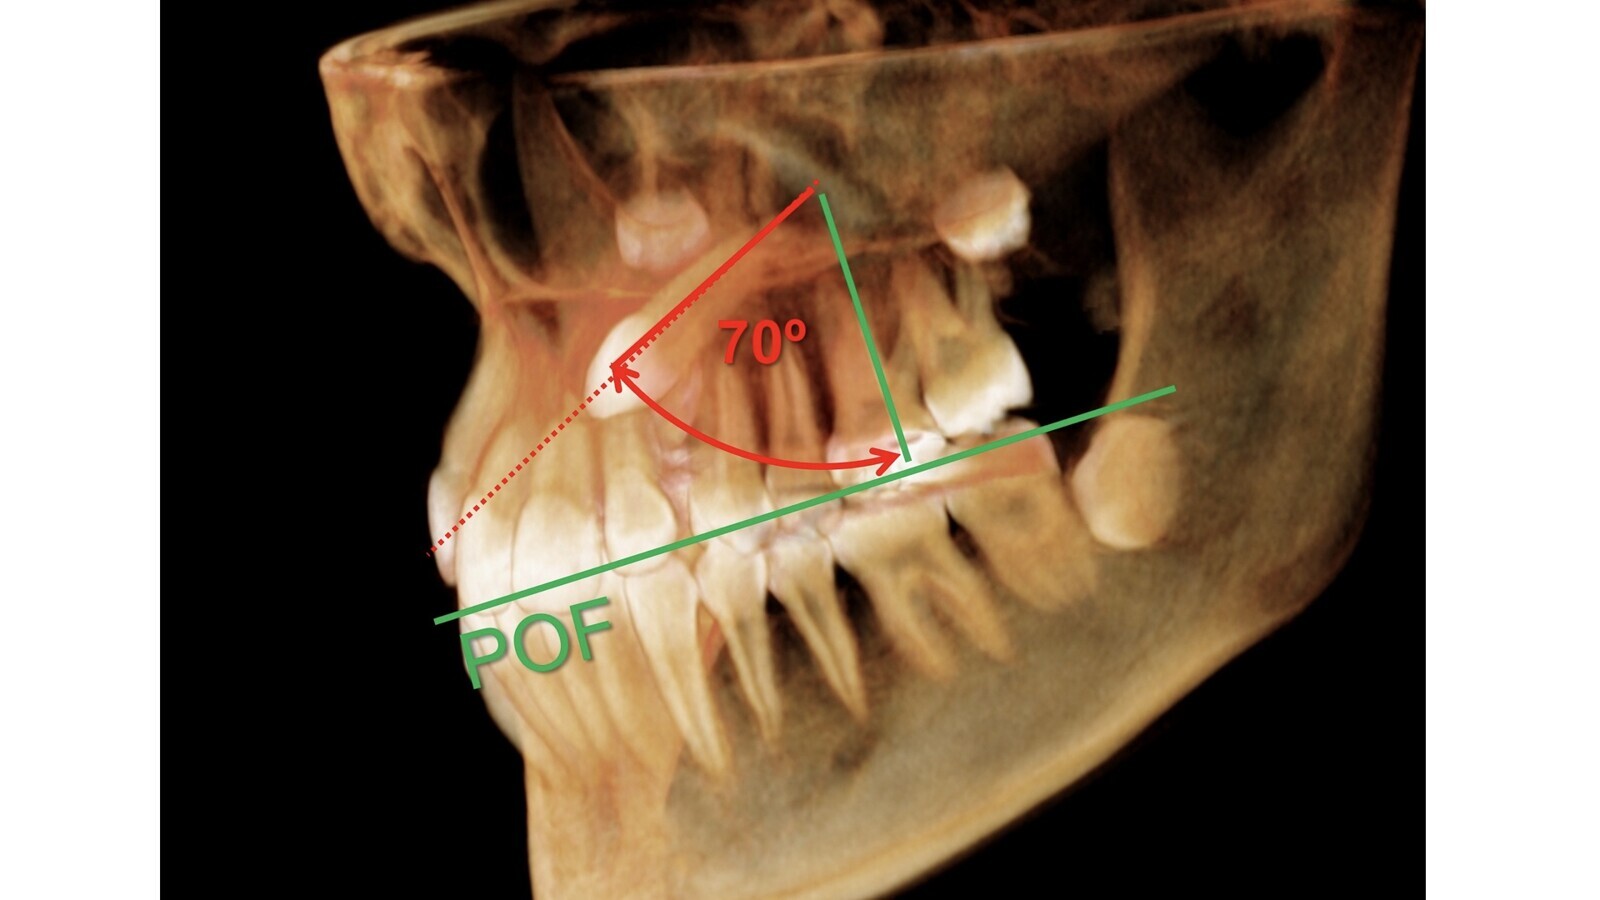

Las tablas pronóstico que presentamos son una aproximación clínica y subjetiva al problema; no derivan de una investigación rigurosa, sino de ese feeling que los clínicos vamos atesorando en nuestra mente tras acertar algunas veces y fracasar muchas. Ayudarán a que el clínico experimentado, curtido por los años, mande extraer menos caninos incluidos, al menos los de mejor pronóstico, y a que el novato no se meta en misiones imposibles que acaban en un desagradable conflicto con el paciente tras robar muchas horas de sueño al profesional. O cruzamos el río o no lo cruzamos, pero lo peor es quedarse en mitad de la corriente y que ésta nos arrastre hacia la catarata. Ni que decir tiene que el CBCT/TAC es crucial en el pronóstico del problema, es el arma diagnóstica definitiva. Hay que pensar siempre en los tres planos del espacio y entender que la mayoría de los caninos se mueven en un espacio cónico cuyo vértice se localiza en la parte más apical de la fosa canina; cuando el canino se sale de este espacio cónico virtual hay que ir pensando en darlo por perdido (figura 4).

Figura 4. Medir la angulación del canino y la altura de su corona se puede realizar a partir de una perpendicular al plano transversal maxilar.

En el plano frontal (figura 4) hay que valorar la angulación del canino y la altura de su corona. Medir la angulación se puede realizar a partir de una perpendicular al plano transversal maxilar, siendo el ángulo de 0º cuando el canino en cuestión está vertical y de 90º cuando el canino está completamente horizontal y está paralelo al plano transversal maxilar referido. A mayor ángulo, mayor puntaje negativo a la hora de valorar la dificultad del caso. Para valorar la altura de la corona (figuras 5 y 6), hemos establecido aleatoriamente tres áreas rectangulares:

I (desde borde gingival de incisivos superiores a la mitad radicular),

II (desde el área I hasta el tercio radicular apical), y,

III (desde la unión del tercio apical de la raíz con los dos tercios restantes hasta más allá del ápice radicular).

Figuras 5 y 6. Para valorar la altura de la corona (figuras 5 y 6), se han establecido aleatoriamente tres áreas rectangulares.